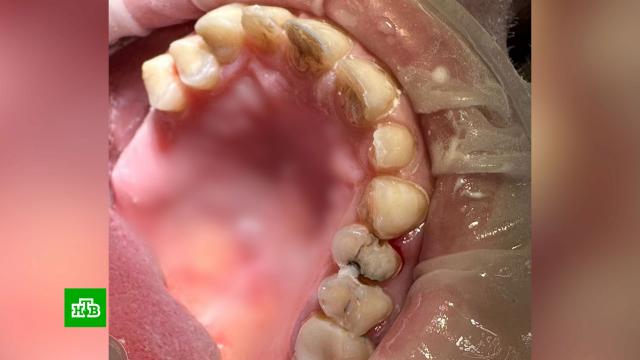

Анна Березовская, пострадавшая: «Наталья мне сказала: „Зубы отбеливать не нужно, это испортит твои зубы. Я тебе сделаю реставрацию, у меня все московские делают“. На третий день у меня уже пошли огромные черные пята на передних зубах, на что я к ней неоднократно обращалась. Она меня заверяла, что это не окончательный результат. В данный момент мне сделали зону улыбки. Отдала я ей 80 тысяч и 270 тысяч я отдала клинике, огромное им спасибо, которые вообще взялись исправлять».

Только сейчас Артём Инчеров признается, что может спокойно жевать. Ошибки

Артём Инчеров, пострадавший: «Сколько коренных зубов пришлось удалить и во сколько это все встало».